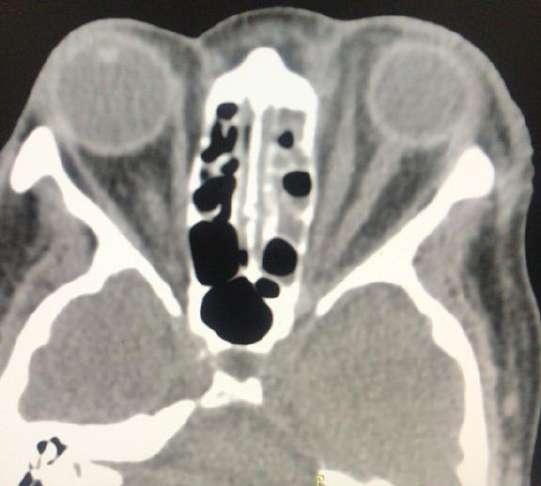

2.C. TUMOR DE CUERPO CAROTÍDEO + OCLUSIÓN DE RAMA ARTERIAL

TAC (imagen B): Tumor de cuerpo carotídeo derecho, shamblin III

A B

RETINAL CON ISQUEMIA MACULAR OD

Caso aportado por Dr. Cristian Sánchez

Clínica:

AV: OD CAE =0,2 / OI 0,8

PIO: OD 10/ OI: 16

BMC: Polo anterior normal

FO: Oclusión de la arteria ciliorretinal con isquemia macular OD

Obstrucción de la arteria ciliorretinal (OACR)

ü La arteria ciliorretiniana esta presente en 15-30% de los ojos

ü Es rama de arterias ciliares cortas posteriores

ü La etiología de la OACR suele estar relacionada con enfermedad carotídea u otros procesos tromboembólicos relacionados con estados de hipercoagulabilidad y autoinmunidad.

ü El diagnóstico suele ser fundoscópico con la visualización en nuestro caso del área retineana isquémica en el terrirotio de la arteria ciliorretineana y la visualización del embolo.